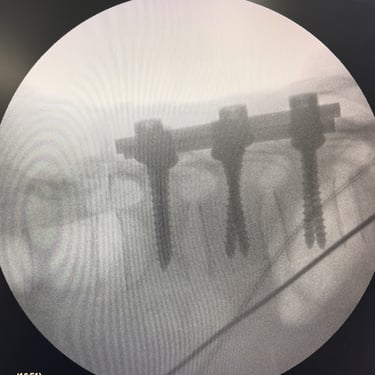

Fractura Vertebral Lumbar: Estabilización Segura con Fijación Transpedicular (FTP)

La fractura vertebral lumbar es una lesión que puede comprometer la estabilidad de la columna y las estructuras neurológicas. En casos seleccionados, el tratamiento quirúrgico mediante artrodesis con fijación transpedicular (FTP) ofrece una estabilización sólida de los segmentos afectados, restaurando la alineación vertebral y permitiendo una movilización temprana. Esta técnica reduce el dolor, previene deformidades progresivas y protege las raíces nerviosas. La intervención oportuna, acompañada de una adecuada rehabilitación, contribuye a una recuperación funcional segura y a una mejora significativa en la calidad de vida del paciente.